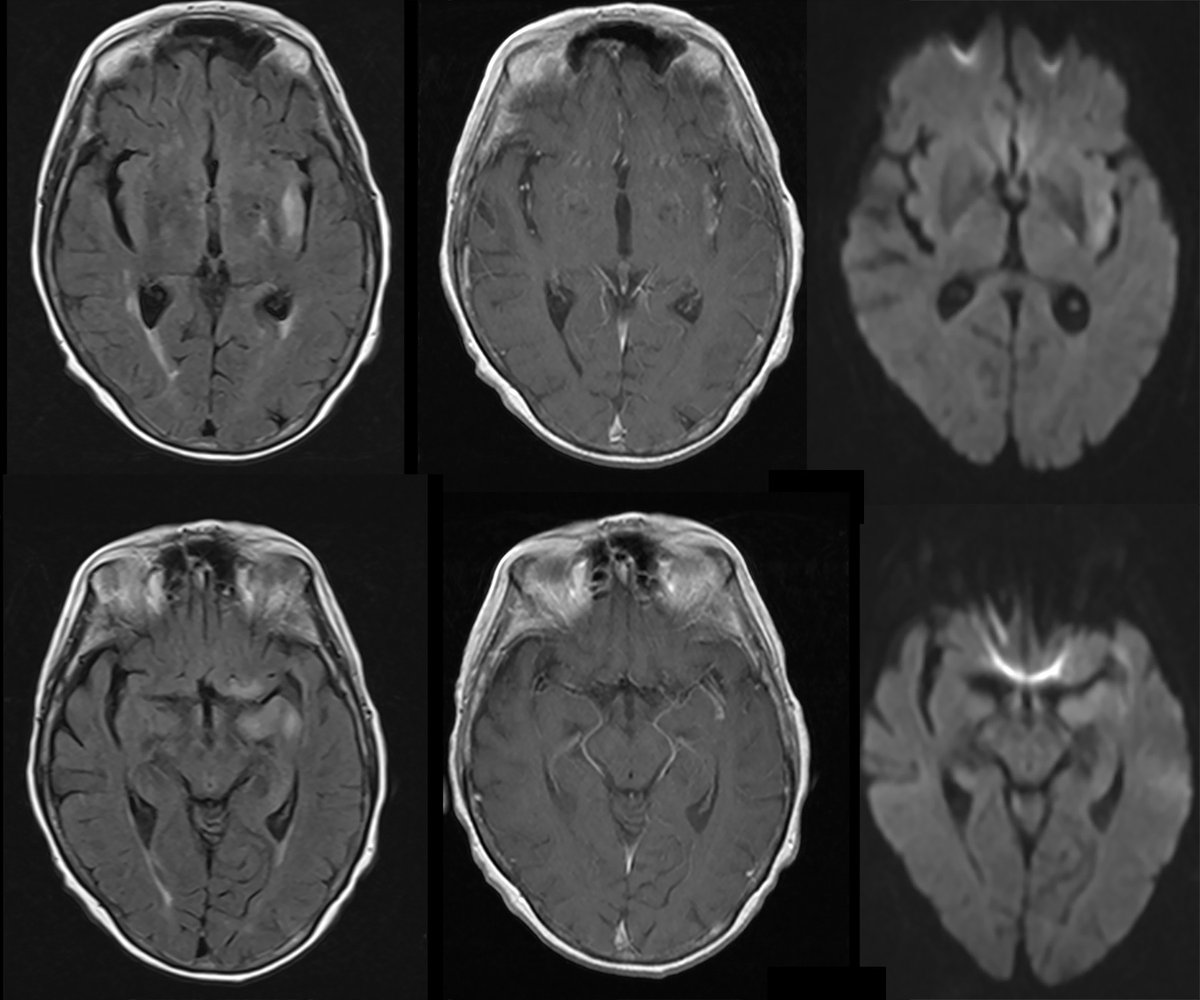

Emory Radiology COTD #108 Hx: Young adult w/ headaches NO SPOILERS!! Don't give answer away or you will be blocked. Give hints w/ GIFs only. Follow case response policy Submit to http://bit.ly/EmoryCOTD Answer in 24 hrs

#Neuro#Neurorad#FOAMrad#FOAMed#radres#EmoryRadCOTDpic.twitter.com/4XIH2CQQMO

#radres#Neurorad#Neuro#FOAMrad#FOAMed HSV encephalitis, MUST make diagnosis: involvement of the limbic system, insular cortex, medial temporal lobe, and inferior frontal lobe@UCLANeurorads@TheASNRpic.twitter.com/87gi7tZpdq